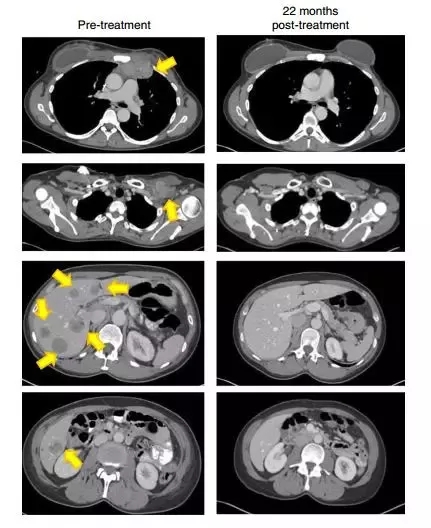

晚期乳腺癌CT图片_圈子_医脉通

肿瘤浸润淋巴细胞疗法,重新”唤醒”体内的免疫细胞后,这些晚期患者的肿瘤都消退了_全球肿瘤医生网

晚期乳腺癌CT图片_圈子_医脉通